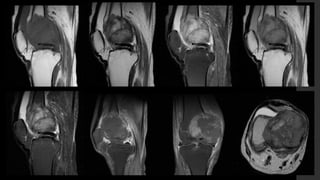

Tumor de Células Gigantes.

• IRM 

 T1 

 Componente sólido con señal intermedia a baja.

 Periferia con señal baja.

 T1+C 

 Realce de los componentes sólidos (lo distingue del quiste óseo aneurismático).

 Puede mostrar realce en la médula ósea adyacente.

 T2 

 Señal alta heterogénea con áreas de señal baja (debido a hemosiderina y fibrosis).

 Si hay componente quístico óseo aneurismático puede mostrar niveles líquido – líquido.

 Si hay señal alta adyacente a la médula ósea puede deberse a edema.